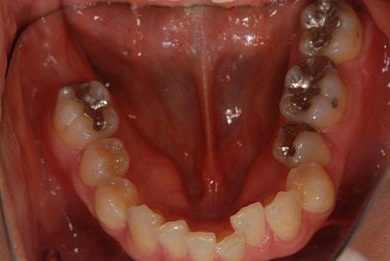

| 性別/年齢 | 女性 / 37歳 | ||||||||||||||||||||||||||||||||

| 主訴 | 左奥歯を抜歯した際、インプラントをするにはほおの一部を移植すると言われたが、他の先生の意見を伺いたい。 | ||||||||||||||||||||||||||||||||

| 治療内容 | インプラント1本、メタルボンドセラミッククラウン1本 | ||||||||||||||||||||||||||||||||

| 総治療費 | 252,000円 | ||||||||||||||||||||||||||||||||

| 治療期間 | 6ヶ月 |